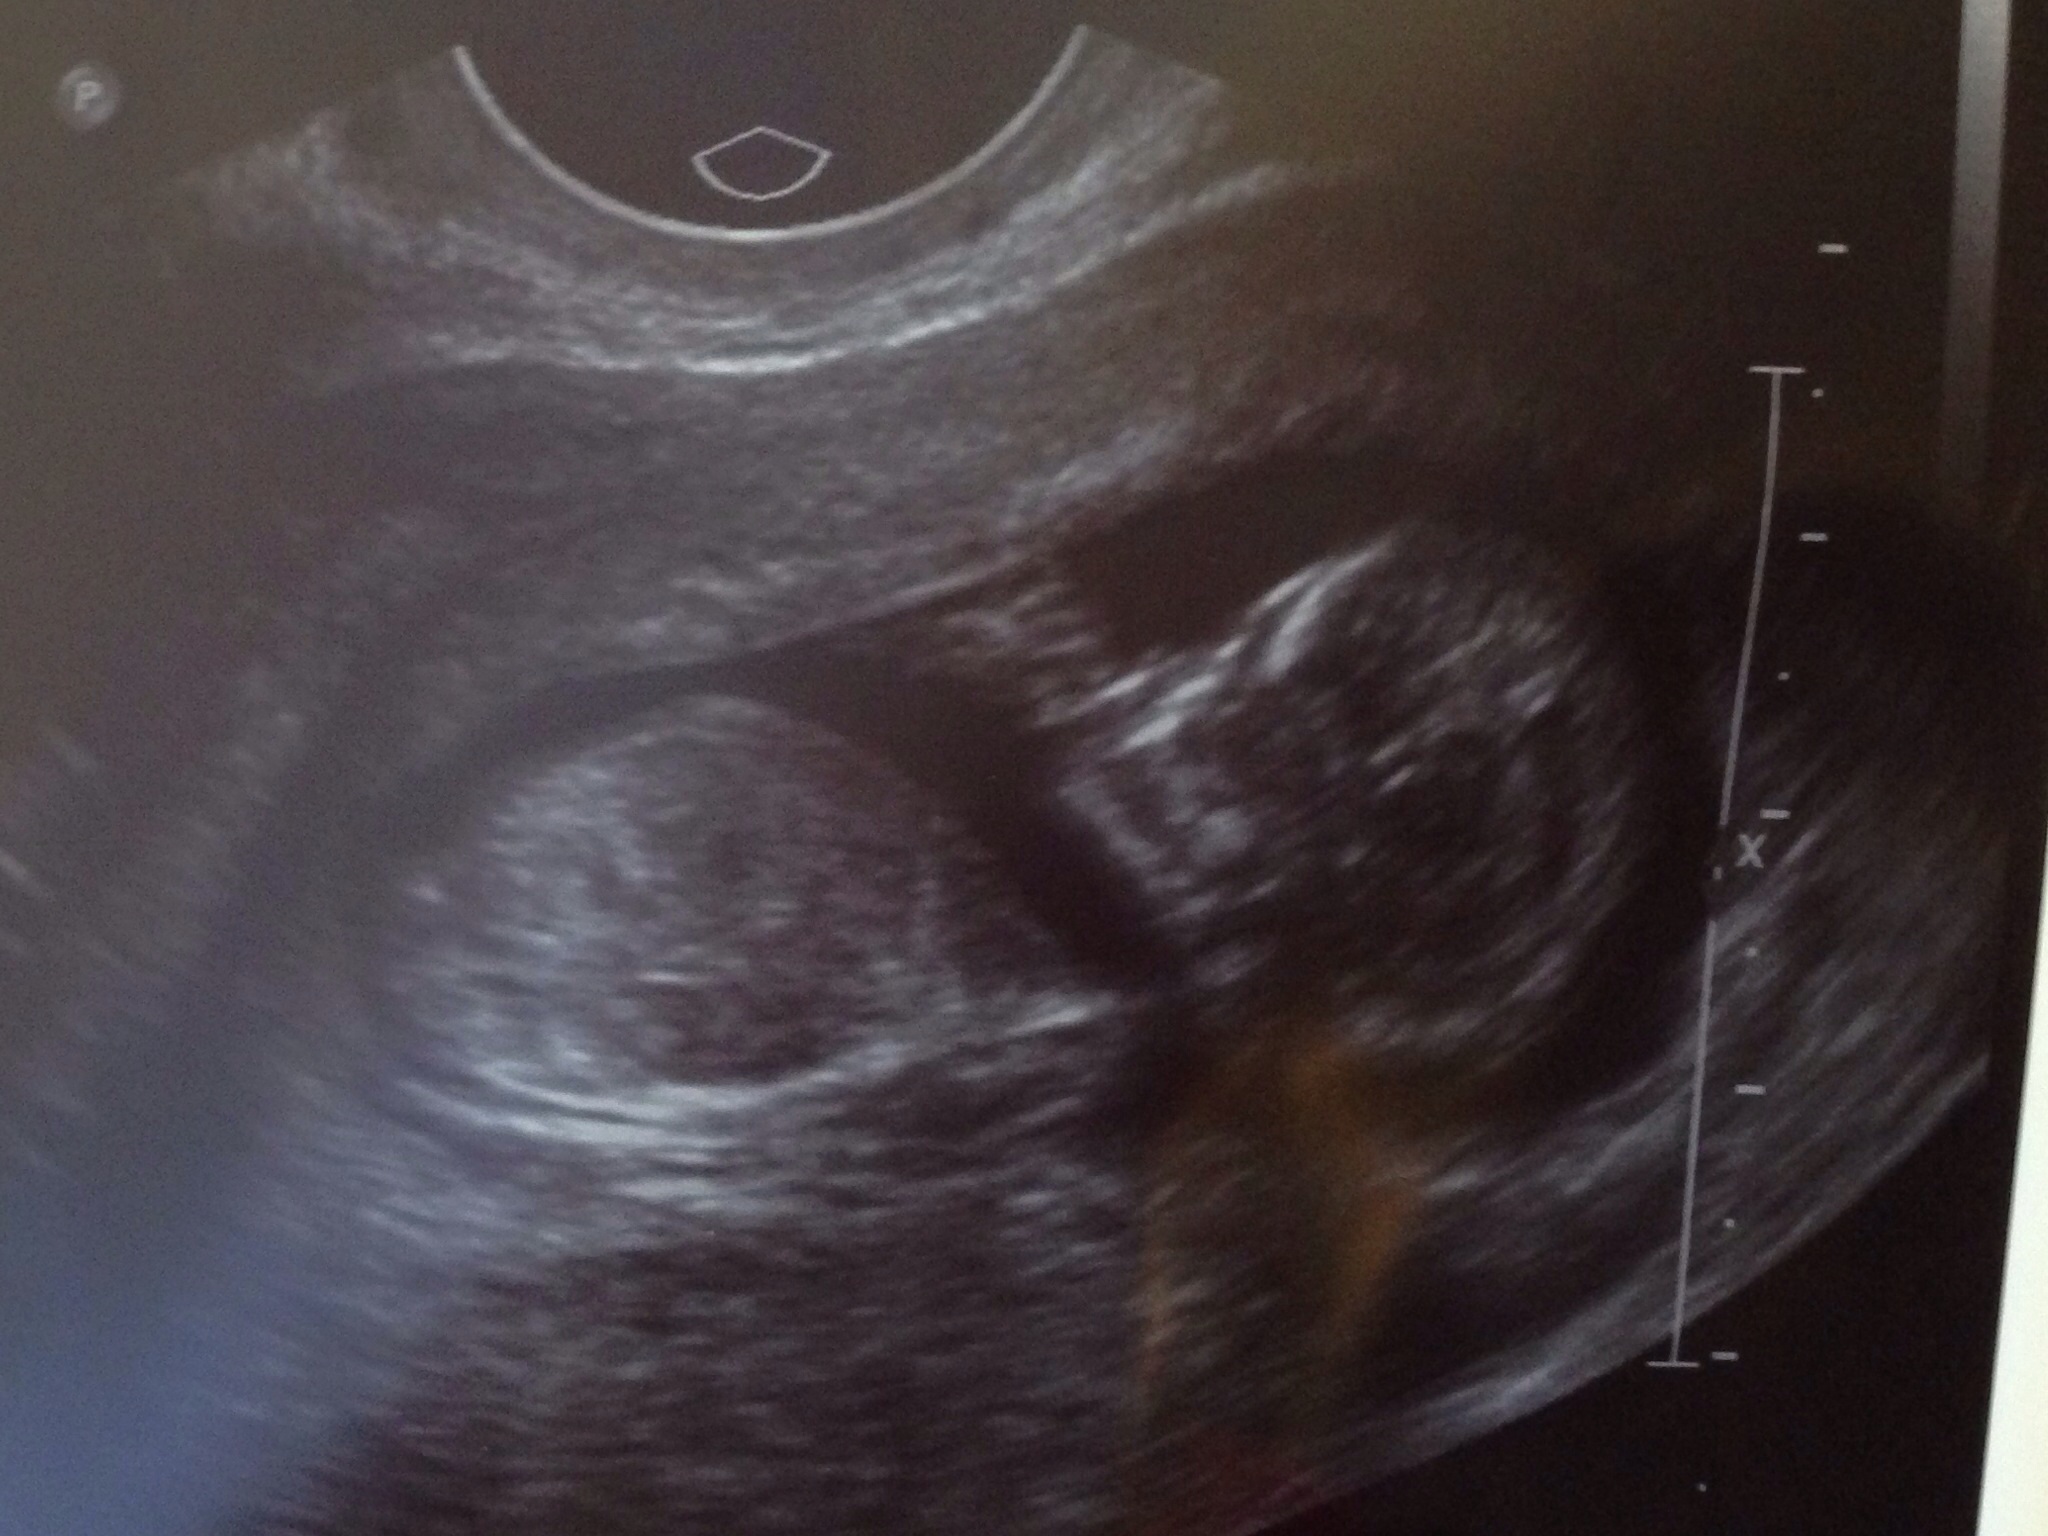

Found out We're having a BOY!!

Went in for our office visit today and was surprised that the u/a tech was able to see the sex of our baby!!

We are so excited!

She didn't post a picture of the goods (or rather lack of since it is so early). It's just a regular ultrasound picture.

• Honestly not trying to be a debbie downer, but 12 weeks is way too early to tell unless you had a CVS or some other DNA testing done.  At this point it is still 50/50 chance it's a boy.

• I mean, follow up at 20 weeks, BUT:

All babies have a visible "nub" at this point. They look about the same, but nubs that turn into boy parts point up (angle greater than 30 degrees), girl nubs (clitoris) point down. 99% accurate by 12 weeks, but your tech has to be up on the latest research and know what they're looking for. I can post the paper from the computer but I'm on mobile now.

We also received results from a blood test today. My u/s tech has also been doing this for 17 years so I trust her.

• I'm not a first time mom...I have a son and a daughter :) We also received results from a blood test today. My u/s tech has also been doing this for 17 years so I trust her. I'm sorry if you've yet to find out but don't rain on our parade :)

• I dont know, there are studies showing sex can be determined with a high level of accuracy at 12 weeks by measuring the angle of the genital tubercle. But I would still secodn guess how good the tech was or how good the machine's measurements were. So while I do think science says it is possible to tell the sex at 12 weeks from ultrasound, I wouldn't paint the nursery yet either. https://www.ncbi.nlm.nih.gov/m/pubmed/10380292/

Congrats, if you received results from a blood test that showed the chromosomes and it was a boy then you have a boy, don't even need an US for that.